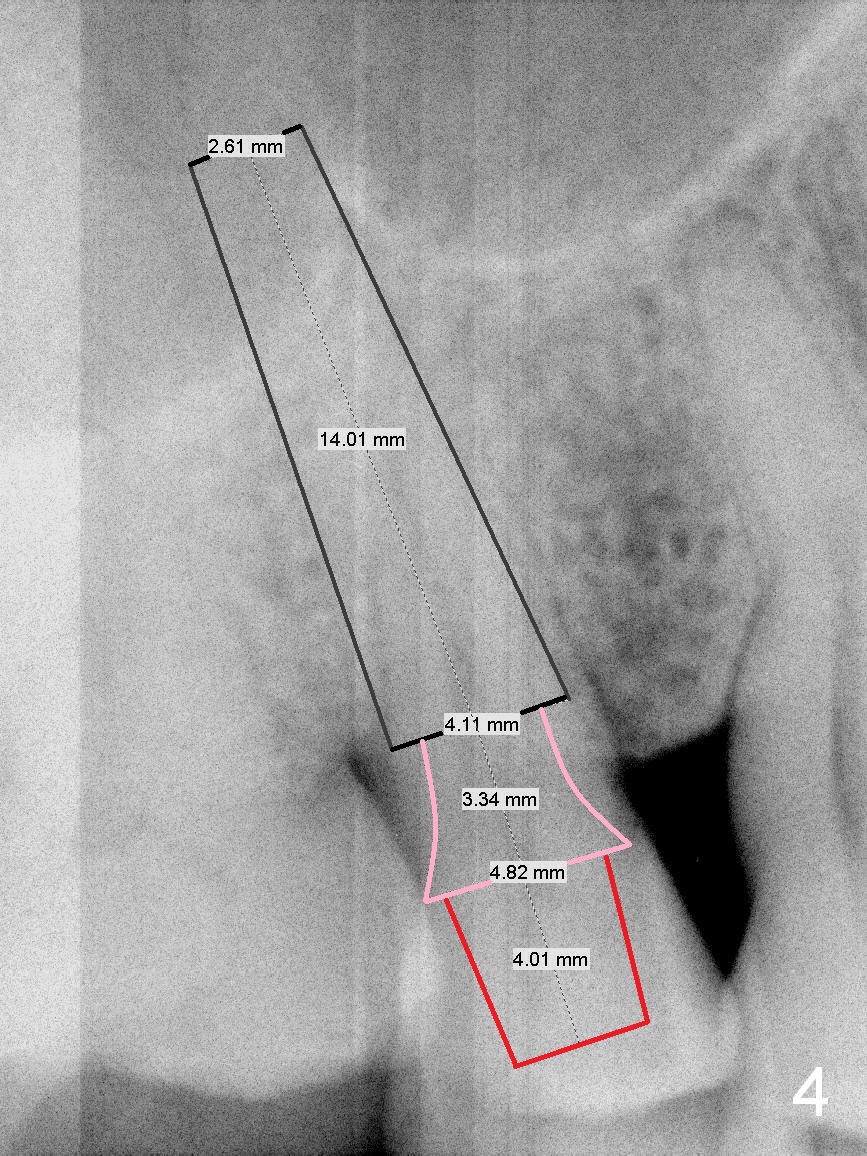

A 61-year-old man (WJ) cracked the tooth #31 after RCT. Four years after #31 extraction, the tooth #4 cracks by itself. The apex of the tooth appears to protrude into the sinus and is closely associated with the sinus septum (triangle: Fig.2,3). An implant will reach the top of the socket for stability (Fig.4 black area). The abutment is expected to be 4.8x4(3) (SM) or 4.5x4(3) (UF) mm. Metronidazole will be used for disinfection of the socket. On returning, he requests #31 implant.